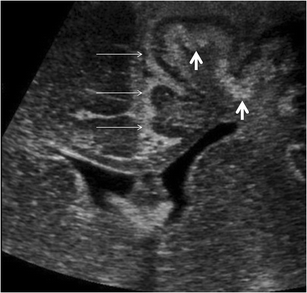

Pre- and postnatal imaging of early cerebral damage in Sturge-Weber syndrome

A case of prenatal diagnosis of Sturge-Weber syndrome associated with polymicrogyria is reported. The diagnosis was based on a unique association with unilateral hemispheric gyriform calcification, focal hemispheric atrophy and white matter changes on prenatal imaging including ultrasound and MRI. Polymicrogyria, which is exceptionally associated with Sturge-Weber syndrome, is suggestive of and reinforces the hypothesis of early impairment of the cerebral microvasculature related to leptomeningeal angioma, which may lead to abnormal cerebral development as early as the second trimester of pregnancy.

Fig. 4